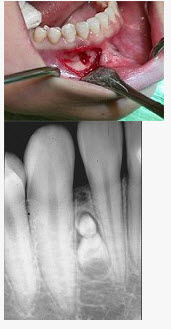

组图为牙瘤的外观及X线表现,有关此病的描述错误的是()

A、多见青年人

B、生长缓慢,早期无自觉症状

C、由牙胚组织异常发育增生而形成

D、X线可见类似发育不全牙的影像

E、绝大多数为恶性

E